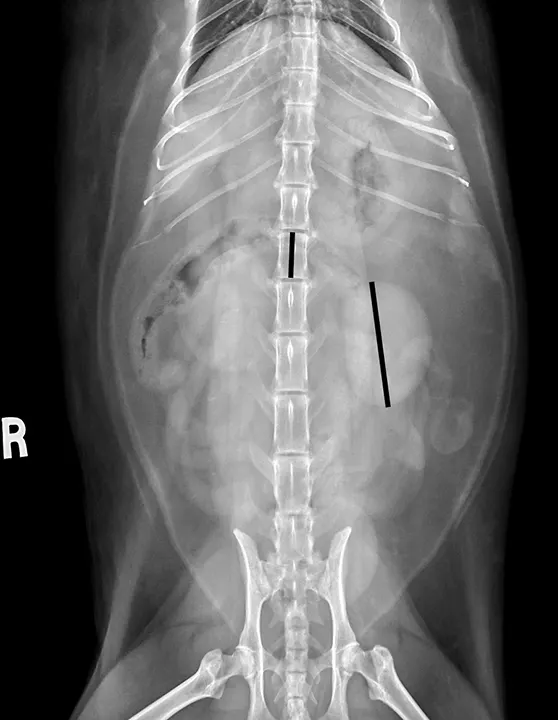

FIGURE 5

Ventrodorsal radiograph measuring renal size of normal kidneys in a neutered cat. The longer black line over the renal silhouette shows the length of the left kidney, which can be compared with the shorter black line superimposed on the L2 vertebral body.